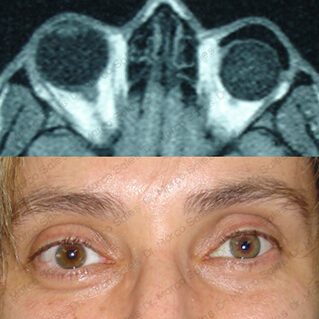

ORBITOPATÍA TIROIDEA